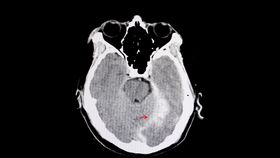

TBIs are very common in contact sports such as American football, rugby, and soccer, where players hit the ball with their heads, as well as other physical contact sport like wrestling or mixed martial arts. However, quickly evaluating if someone has experienced a TBI has been challenging. Patients usually end up going to hospital a fair period of time after experiencing the injury, as there is no current immediate evaluation test available. The diagnosis of a TBI currently requires a person to go to hospital for a CT scan after they experience symptoms of a concussion, and then receive the scan to rule on whether they have a TBI.

Now the Abbott handheld device is set to change that, allowing for rapid testing after a suspected concussion that could deliver the results within 15 minutes. A negative test using the handheld device could rule out the requirement of getting a CT scan to test for a TBI, a positive result would mean they should get a CT scan to confirm if it is a TBI and how severe it is so that they can get the clinical care they need.